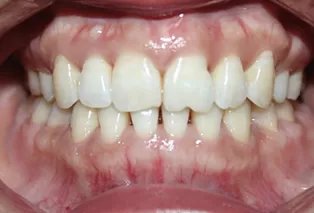

Intraoral photos after treatment